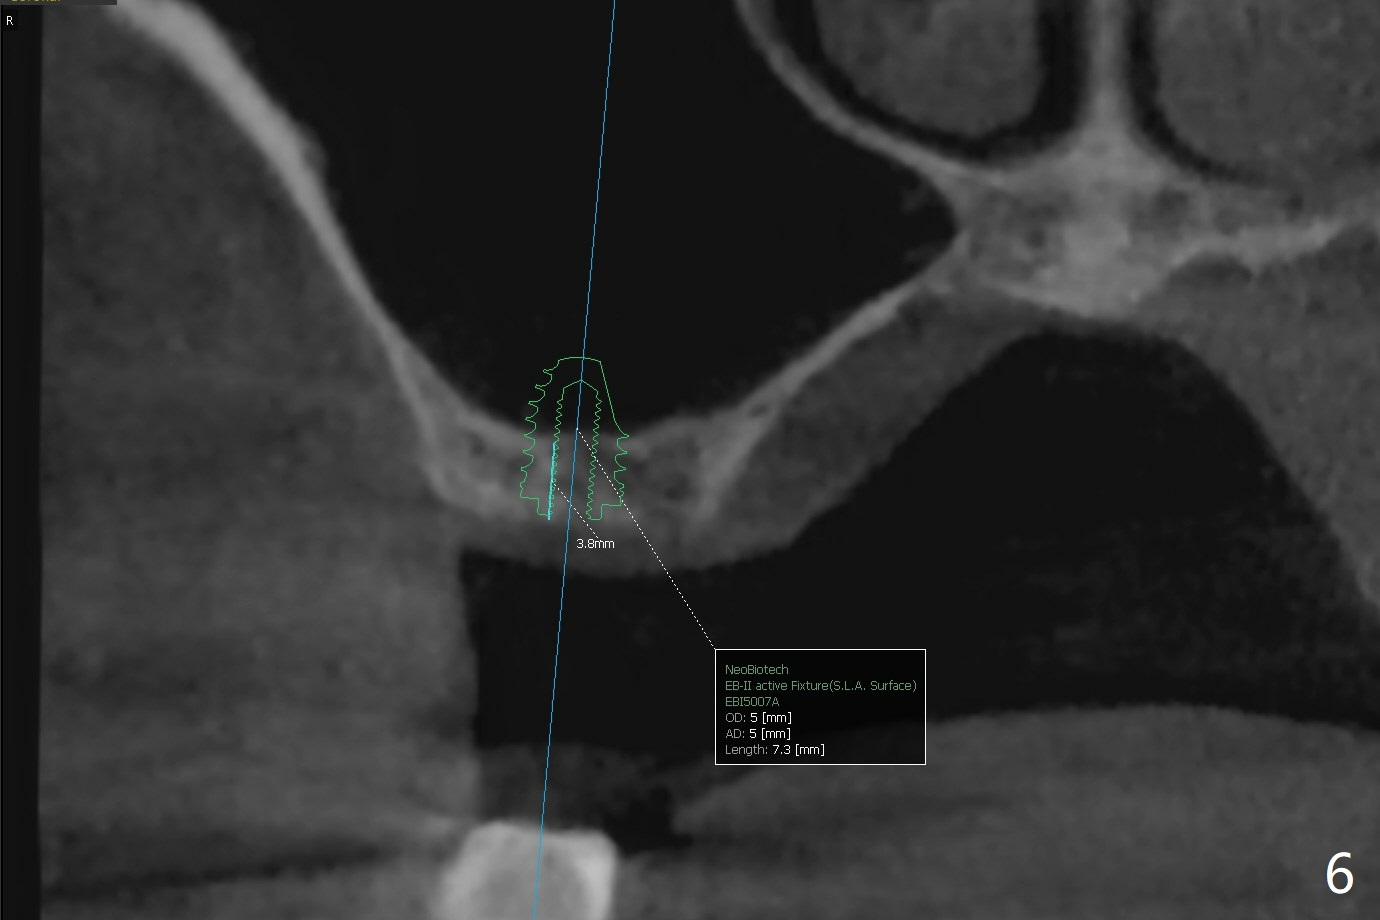

A 72-year-old man agrees to have #14 to be extracted for implant (Fig.1). In the first stage, impression is taken for #14 and 18 implant placement with guide. Due to odontogenic sinus infection (Fig.1,2 *), Z pack will be taken to prevent implant infection associated with sinus lift (Fig.2). Remove provisional and abutment once the sockets heal. To combat #15 supraeruption, the implant at #18 will be placed deep; if the torque is high, place a large diameter healing abutment or provisional with large base will be fabricated so that a short cuffed abutment will be used for final restoration. Heavy occlusal reduction at #15 will be conducted (Fig.3 curved lines). In spite of the fact that the bone height at #3 is 3-4 mm, the sinus floor is flat (Fig.4). Internal sinus lift is not expected to be too difficult. Use Magic Sinus Lifter, followed by implant placement at the same stage (Fig.5,6).